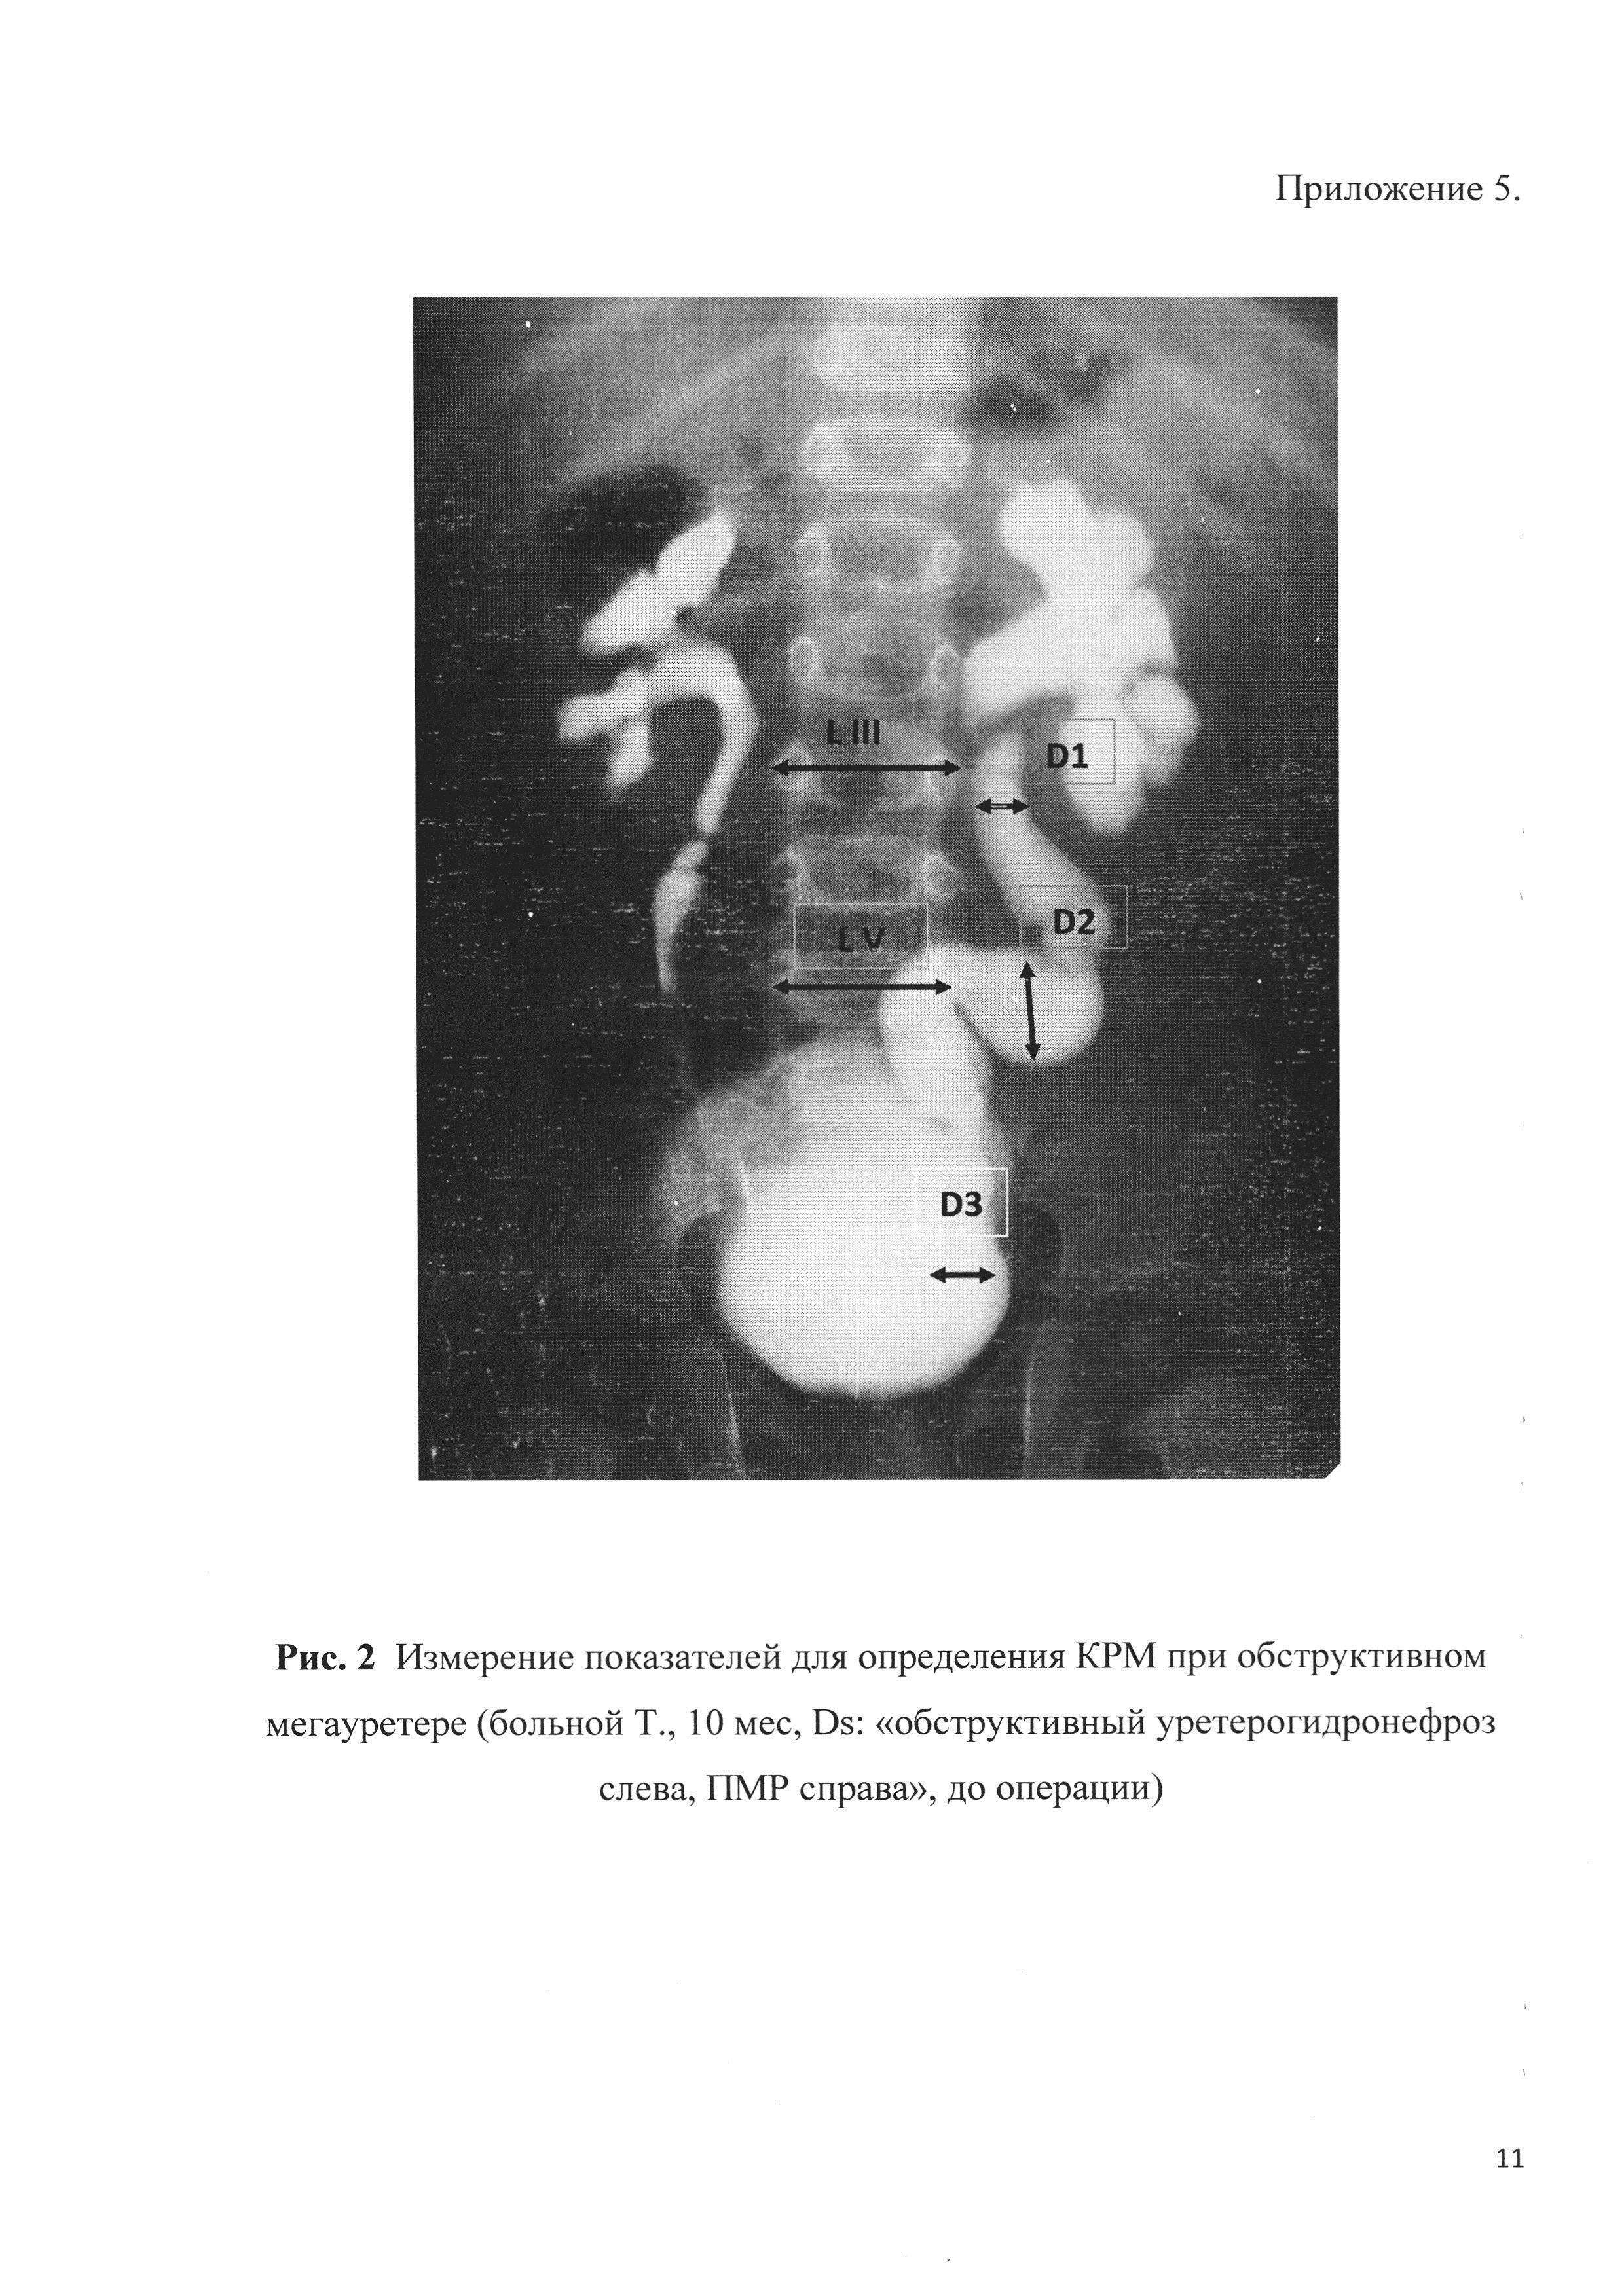

Медицинские изображения и примеры эксреторной цистографии